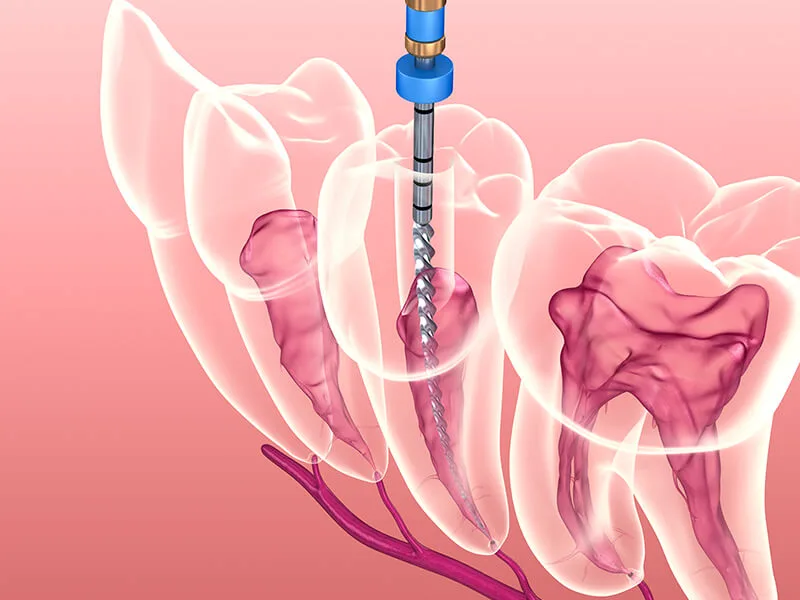

Uma clínica com especialista em endodontia oferece intervenções que são pautadas pela precisão técnica. Isso se deve à formação específica e ao conhecimento aprofundado do profissional sobre a anatomia das raízes:

Remoção completa da polpa infectada ou inflamada;

Limpeza e desinfecção profunda dos canais radiculares;

Uso de materiais biocompatíveis para uma obturação estável.

Essas etapas são fundamentais para eliminar focos bacterianos que podem atingir o osso alveolar. O rigor técnico em cada detalhe do processo evita recidivas e protege a integridade do elemento dental tratado.

Ferramentas como localizadores apicais e sistemas rotatórios aumentam a eficiência da limpeza interna dos canais. A tecnologia aliada ao conhecimento técnico resulta em uma recuperação ágil e com menores chances de intercorrências.